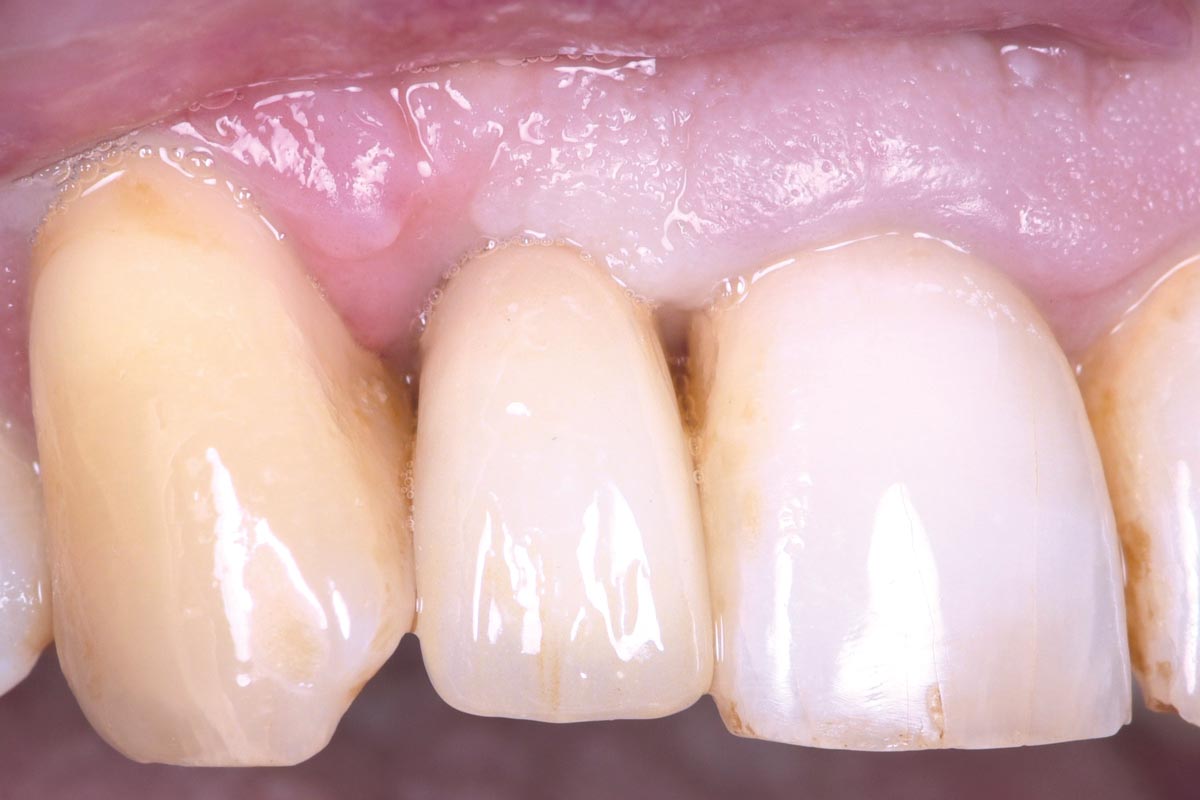

12/13 - Clinical situation 4 months post surgery: Excellent hard and soft tissue adaptation, papilla closing bilaterally

Immediate implant placement in the maxilla with contour GBR - Dr. K. Loukas